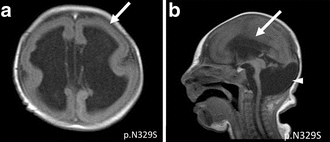

a-c)T1 and T2 image- microlissencephaly -

MRI of a patient with a TUBA1A mutation showing microlissencephaly with cerebellar hypoplasia. a. smooth brain surface (arrow) b. absent corpus callosum (arrow).